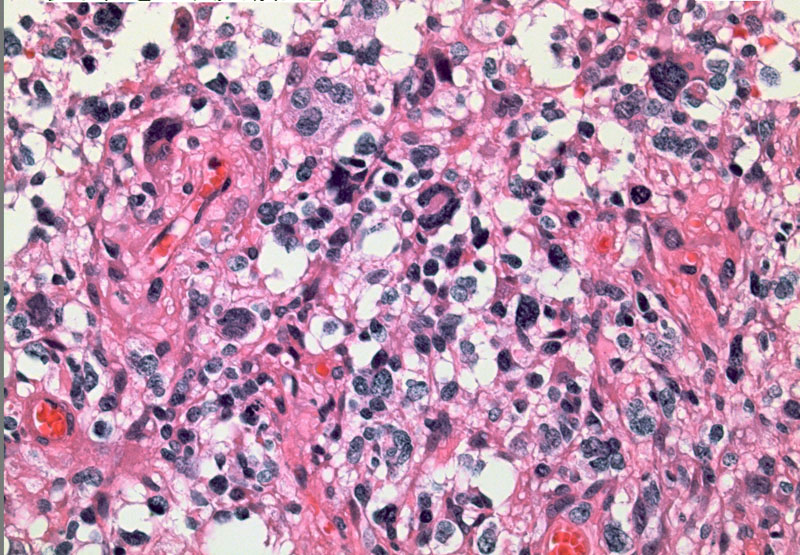

glioblastomahe2

これは普通の病理組織診断です。これだけで膠芽腫という診断はつきます,

bizarre! 異様な細胞が混在しています。核多型が目立ち,多核巨細胞も混じる典型的な膠芽腫の像です。下の左の画像は血管内皮の肥厚 endovascular proliferationがあり,下の右のKi-67染色では核濃染像が多く核分裂能が高いことを示します。しかし,——